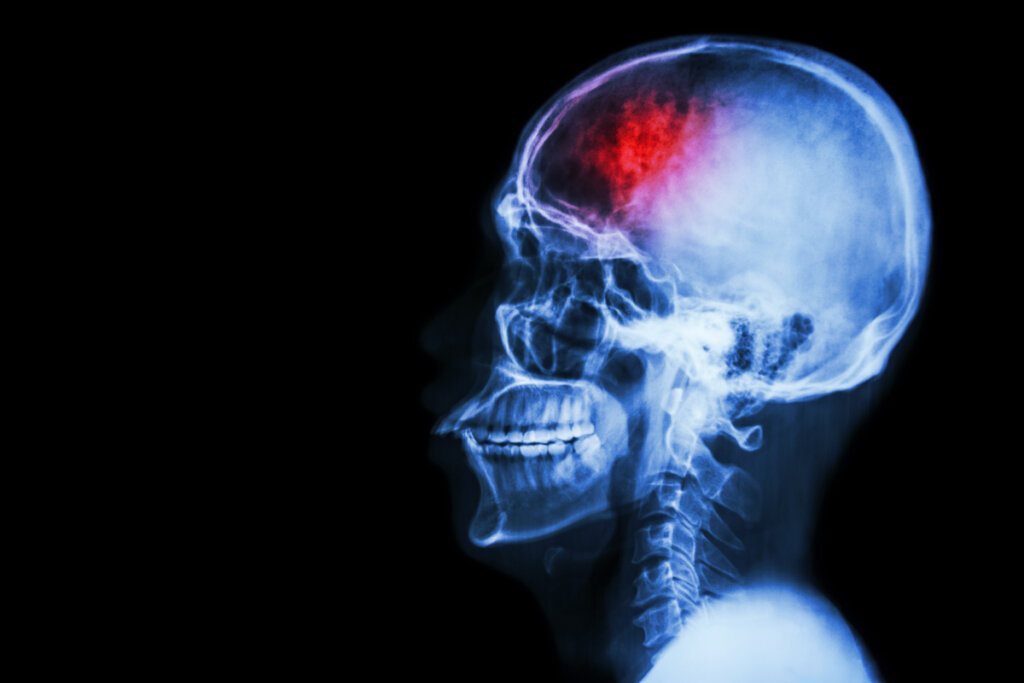

Executive dysfunction isn’t a disorder in itself, but a deficit that can appear in different conditions. At the neurobiological level, executive function is directly associated with the prefrontal cortex. This brain region develops primarily during childhood and adolescence. Indeed, it’s at these stages that youngsters develop and perfect these abilities.